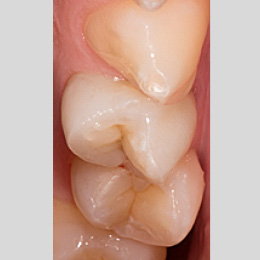

Fallbeispiel: Zahn 14 mit 3 Kanälen

Unbehandelte Wurzelkanäle – eine der häufigsten Ursachen für persistierende Infektionen nach einer Wurzelkanalbehandlung. Mit einer Revisionsbehandlung können unbehandelte Kanäle behandelt und der Zahn erhalten werden.